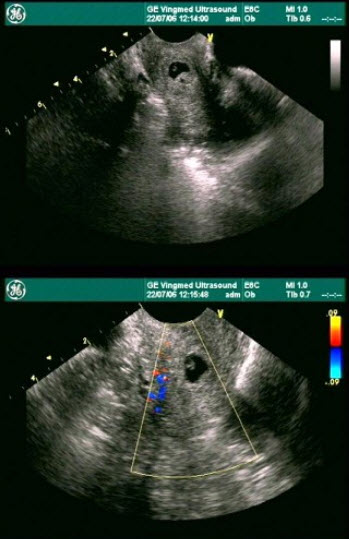

65、单项选择题

女性,27岁,停经49天,尿妊娠试验阳性。如图所示,超声诊断为()

A.宫腔积液

B.早孕,多胎妊娠

C.绒癌

D.葡萄胎

E.稽留流产